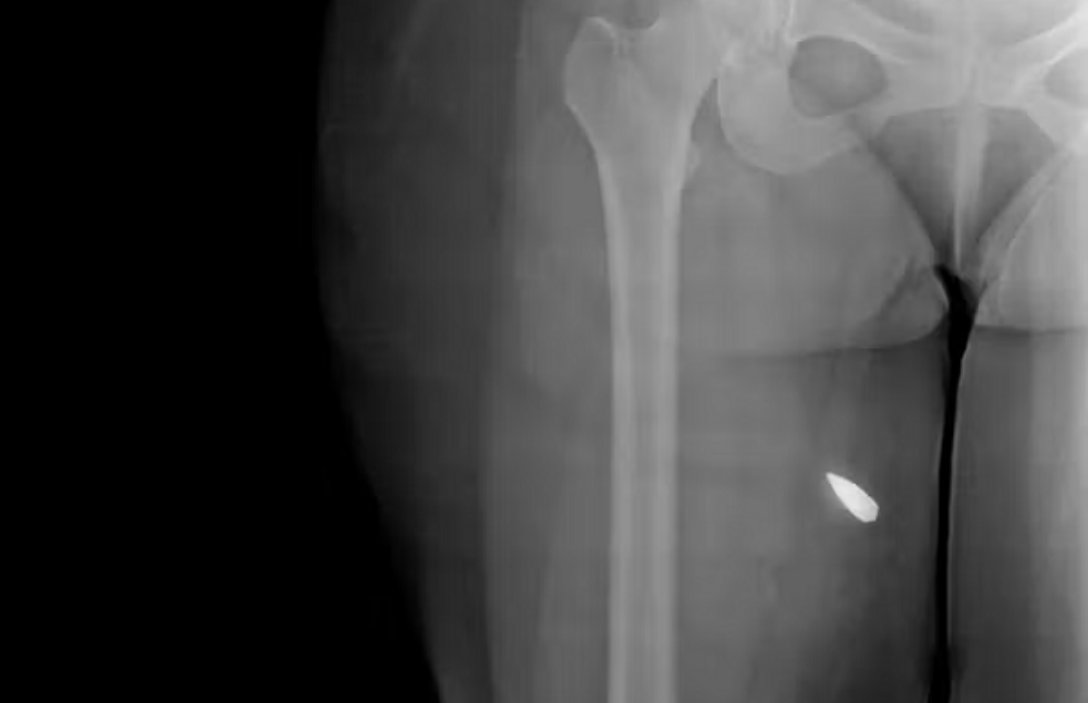

Le scansioni mostrano corpi colpiti da pallini metallici e proiettili di grosso calibro. In diversi casi i frammenti sono localizzati in testa, collo, torace e colonna vertebrale. Secondo gli esperti consultati dal Guardian, la distribuzione dei colpi e la loro profondità indicano l’uso di armi ad alta velocità e, in alcuni casi, di munizioni “full metal jacket”, tipicamente impiegate in fucili d’assalto.

Le immagini evidenziano lesioni cerebrali penetranti, perforazioni polmonari, danni alla trachea e fratture complesse. In alcuni pazienti i proiettili risultano ancora visibili all’interno del corpo. Medici interpellati parlano di ferite compatibili con spari a distanza ravvicinata. “Con questo tipo di armi l’intento è letale”, ha dichiarato uno degli specialisti che ha esaminato il materiale.

Particolarmente rilevanti sono le lesioni agli occhi, al bacino e ai genitali. Diversi pazienti presentano concentrazioni elevate di pallini in queste aree, con conseguenze permanenti possibili: perdita della vista, danni agli organi interni, infertilità. Alcuni casi mostrano centinaia di frammenti metallici distribuiti nel torace o negli arti inferiori.